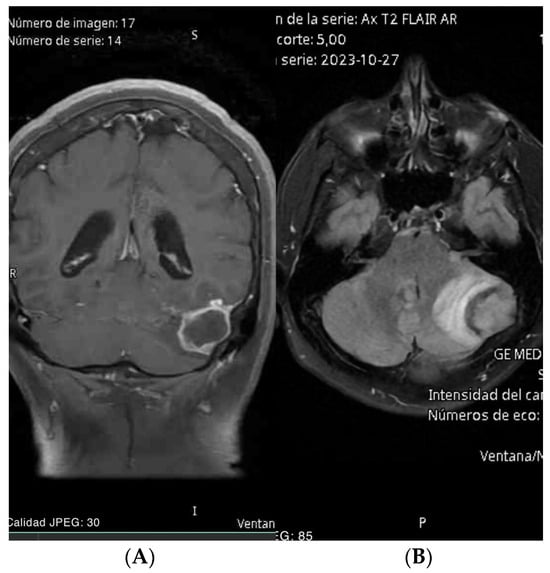

- Case 3: The use of AR in guiding craniectomy for a pre-rolandic lesion ensured complete resection with excellent functional recovery, demonstrating the precision and effectiveness of AR in locate cortical tumor and the main benefit was knowing the exact topographic relationship of vascular structures where we performed a classic craniotomy and posterior interhemispheric dissection preventing the risk of an inadvertent vascular lesion.